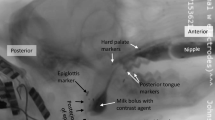

Videofluoroscopic Swallow Study

To quantify changes in bolus flow during swallowing, rats were given chocolate milk (thin consistency) mixed with 40% w/v barium sulfate ad libitum. Animals were acclimated to the testing chamber and testing solution prior to experimental tests. A GE Innova Model 3100 fluoroscope was used at a rate of 30 frames per second. Animals were given 5 min to self-feed and 15-s video clips were taken throughout during notable periods of drinking. Videos were identified for analysis if they included more than three uninterrupted, sequential swallows. A minimum of three separate 15-s video clips per animal were randomly chosen and analyzed using ImageJ (NIH, Bethesda, MD). Swallowing events were identified by advancing frame-by-frame. Measurements were taken of 10–15 different swallows for each rat and averaged. A drinking cannula (within field of view) was used as a calibration marker to appropriately scale images for size analysis. The second cervical vertebra was used to denote the end of the pharyngeal swallowing phase. The following VFSS metrics were calculated as previously described [36, 37]: jaw excursion rate, interswallow interval, lick–swallow ratio, and bolus speed through the pharynx. Bolus area within the pharynx was also calculated for each swallow (mm2) by outlining the barium contrast material at the frame where the bolus was positioned in the oropharynx, immediately after retroflexion from the vallecula. Swallow rate is based off the number of swallows that occurred during a period of uninterrupted drinking at the spout.

To determine differences in jaw movement and pharyngeal swallowing performance, we compared bolus transit 1 and 2 weeks post-injury to baseline function (Fig. 2). Significant differences were found in the jaw excursion rate (cycles/second) after injury [F(2,10) = 6.63, p = 0.02] with decreases observed 1-and 2 weeks post-injury compared to pre-injury (p < 0.03; p < 0.04). There were significant differences in bolus speed through the pharynx [F(2,10) = 7.54, p = 0.01]. At 1 week post-injury, rats exhibited the slowest bolus speed compared to pre-injury (p = 0.02) and 2 weeks post-injury (p < 0.04). Bolus area differed significantly after injury [F(2,10) = 45.63, p = 0.001]. Smaller bolus sizes were swallowed 1 and 2 weeks post-injury compared to pre-injury (both p < 0.001). Lastly, there were significant differences in swallowing rate [F(2,10) = 5.18, p = 0.03] with decreases in frequency found 1 week after injury compared to uninjured and 2 weeks post-injury (both p < 0.04). No statistically significant differences were found with interswallow interval [F(2,10) = 4.07, p = 0.051] and lick–swallow ratio [F(2,10) = 3.28, p = 0.08].

Changes in swallowing metrics taken from videofluoroscopy swallow studies at 0, 1, and 2 weeks post-mylohyoid cryoinjury. Results demonstrate the mean and standard deviations for jaw excursion rate, interswallow interval, swallow rate, bolus speed through pharynx, bolus area, and lick–swallow ratio. Statistical significance of p < 0.05 is indicated by asterisk

Since the tongue and jaw move simultaneously during repetitive licking in the rat [45], we can indirectly measure lick frequency via fluoroscopy by calculating the jaw excursion rate [36] and compare this to bolus transit. Along with reductions in licking frequency, we detected alterations in bolus volume within the pharynx. Bolus size is an indirect estimate of bolus volume [46]. In particular, we found an inverse relationship between bolus size and bolus speed through the pharynx one week after injury. Although bolus speed returned to normal levels two weeks after injury, bolus size during swallowing remained small (− 35% from baseline). One possible explanation for this is that the rats are compensating for a sensorimotor deficit by reducing their bolus volume. When liquid volume during swallowing decreases, less pressure is needed for bolus transport through the pharynx and the relative timing of swallowing events shorten [47,48,49], thus reducing the effort required for swallowing. Previous work in an infant pig model of recurrent laryngeal nerve lesion, which affects vocal fold closure, compared differences between the bolus area in the vallecula and the onset of penetration or aspiration during swallowing [50]. They found changes in bolus size post-lesion, with smaller boluses correlating with increased airway protection. It is possible that sensory adaptations from the nerve injury impacted the central pattern generator (CPG) located in brainstem leading to difficulties in handling the larger boluses safely. The CPG modulates swallowing movement through sensory feedback. Prior work has shown that sensory input from the oral cavity can influence bolus volume and direct the pharyngeal motor response during swallowing [51]. Unlike pigs, rats are not known to aspirate food/liquid. As such, the alterations in bolus parameters found after mylohyoid injury may reflect a means of overcoming challenges found with oral function in order to maintain bolus transit. Our results are consistent with clinical findings, which have shown that patients self-attenuate the effects of a swallowing deficit by reducing their bolus volume per swallow [52]. In further support of a compensatory strategy taking place, a decrease in the frequency of swallows occurred concurrently with the increase in bolus speed one week after injury. The observed changes may relate to alterations in oropharyngeal movement. Swallowing frequency was determined by dividing the total number of swallows by the time between the start and termination of > 3 sequential swallows. Thus, the time accounts for the individual swallowing act and the interval between consecutive swallows. However, the latter was not shown to be affected by injury. To characterize the full extent of differences in functional ability that result from mylohyoid injury, further analysis of swallowing kinematics is warranted.